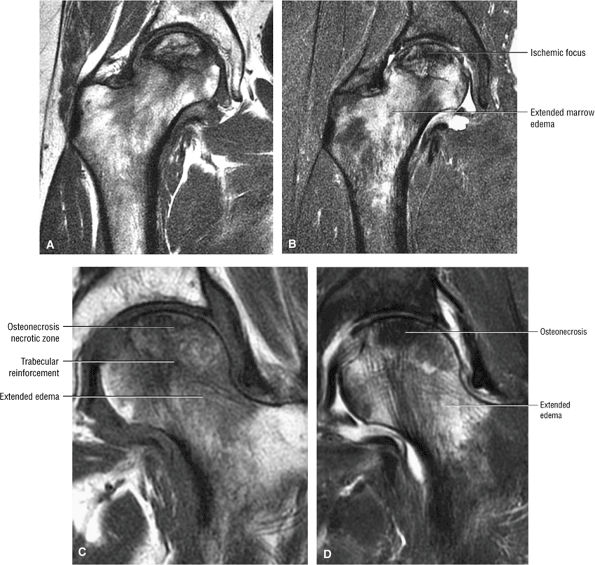

FIGURE 3.81 ● AVN with subchondral fracture. The focus of osteonecrosis involves a portion of the weight-bearing surface. (A) Coronal T1-weighted image. (B) Sagittal T1-weighted image. (C) Sagittal FS PD FSE image.

|